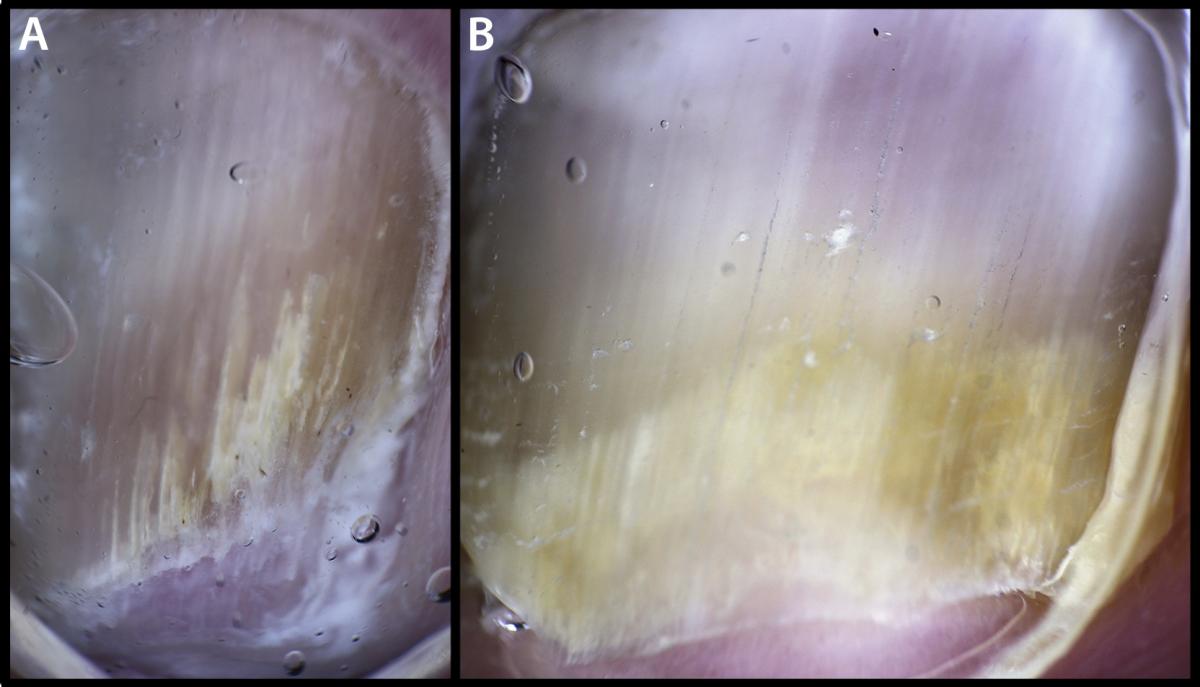

Authors have described the dermoscopic features of onychomycosis.13-15 These features correlate to fungal test results. Short spikes extending proximally from the hyponychial space along with onycholysis are characteristic of onychomycosis. One can often detect these initial changes in onychomycosis with contact dermoscopy coupled to the nail plate with ultrasound gel. The dermatophytic spikes may extend proximally, tunneling under the nail plate along the nail bed grooves as the infection progresses. This dermoscopic evidence of mycotic nail bed infection widens and lengthens into longer yellow striae that extend proximally along the longitudinal rete furrows of the nail bed.

Irregular distal subungual termination and subungual hyperkeratoses also develop. Over time, one may see a so-called “aurora” or “aurora borealis” pattern of many short and centrally longer spikes emerge.14,16 In more severe longstanding cases, a collection of subungual mycotic keratitis may turn into dermatophytoma. These additional features are also significantly associated with positive mycology tests. Typically, multiple sensitive dermoscopic signs of onychomycosis are present in each mycotic nail unit. The most sensitive signs are striae, spikes, aurora borealis and dermatophytoma. In addition, authors have reported irregular termination of the nail plate, onycholysis and opacity as well as subungual ruinous aspect, subungual black dots or globules, and dry or scaling adjacent skin in cases of onychomycosis.13-15

About half of abnormal toenails are not actually mycotic. By utilizing dermoscopy, one can readily differentiate between microtraumatic nail dystrophy and distal subungual and lateral onychomycosis. Point of care diagnosis makes for more accurate diagnoses as well as reduced laboratory costs. The detection of striae, spikes, aurora borealis or dermatophytomas makes the diagnosis of onychomycosis complete.

At least for topical therapy of mild to moderate onychomycosis, treatment can begin immediately without laboratory delay. One can confirm the diagnosis of moderate to severe onychomycosis, requiring systemic therapy, via laboratory tests while waiting for baseline hepatic function panel results. One should suspect microtraumatic nail dystrophy if the onychomycosis striae, spikes, aurora borealis or dermatophytomas features are absent, and there is transverse onycholysis with nail plate opacity. Black dots or globules are additional indicators of microtrauma.13,14